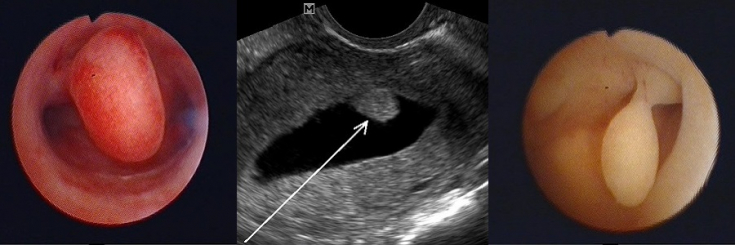

Підтверджений діагноз поліпа ендометрію – пряме показання до призначення діагностичної гістероскопії та проведення гістологічного аналізу одержаних тканин. Перерахуємо основні види оперативних втручань, які застосовуються при лікуванні поліпа ендометрію:

1. Поліпектомія. Проводять за наявності великого одиночного поліпа на ніжці. Тоді його "викручують", а залишкову ранову поверхню припікають електричним струмом або рідким азотом. Ці маніпуляції запобігають, хоч і не завжди, утворенню нових патологічних утворень. Операція проходить швидко, проте проводиться під загальним наркозом.

2. Гістероскопія – видалення поліпа за допомогою ендоскопічного приладу гістероскопа, який вводять через шийку у порожнину матки.